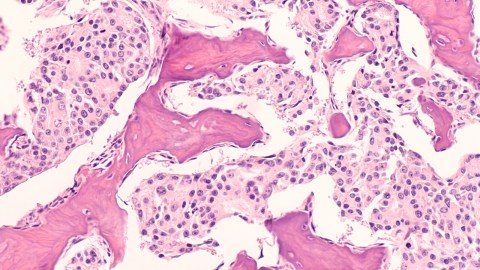

Metastasis, the deadliest and most notorious hallmark of the disease, gives cancer the ability to spread throughout the body, often overwhelming immune defenses and even the best treatments.

Despite being a primary cause of cancer deaths, there’s much about metastasis we still do not know. But now, researchers at the Cancer Research UK (CRUK) Cambridge Institute at the University of Cambridge have discovered a mechanism behind metastasis.

The new research, published in Nature Genetics, identified a cell membrane protein called NALCN that serves as a sodium ion channel and acts as a “key regulator” of metastasis. These channels control the flow of sodium into and out of the cell.

Removing or blocking NALCN activity in mice with cancer “markedly increased the number of circulating tumor cells (CTCs) and metastases,” the authors wrote in their paper.